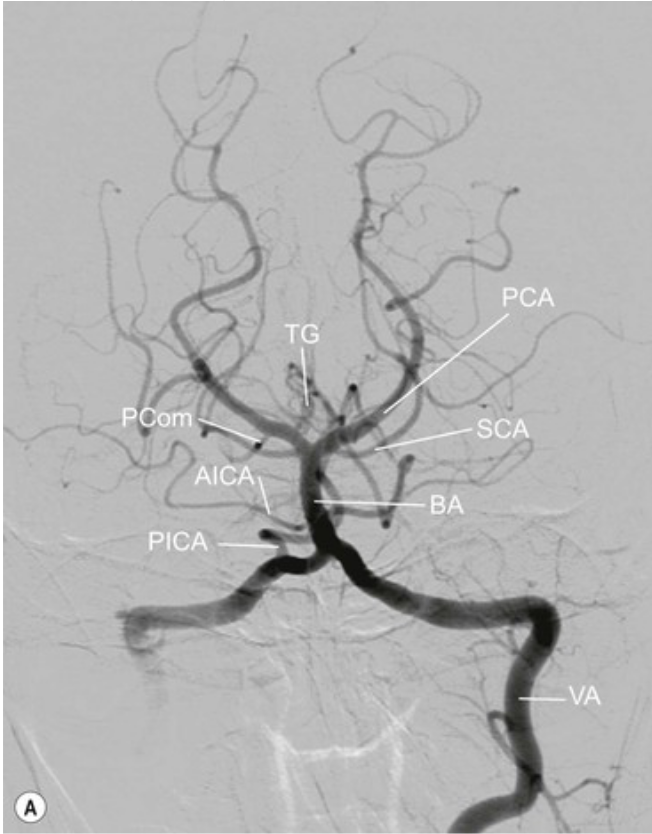

20.1 Patient presents with hemisensory loss and right homonymous hemianopia. Which vessel is affected?

a. Anterior communicating artery

b. Posterior cerebral artery

c. Posterior inferior cerebellar artery

d. Vertebral artery

e. Basilar artery

A

REPEAT

PCA Contralateral